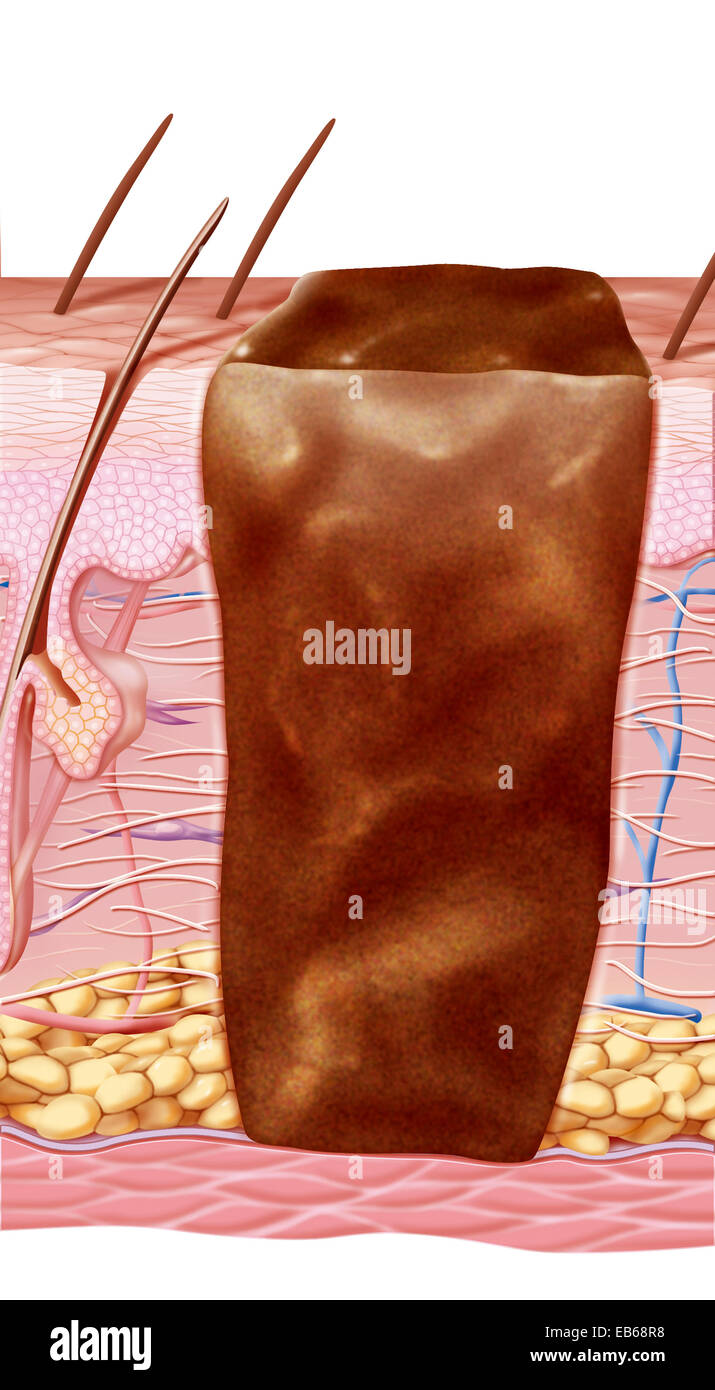

SCAR DRAWING Stock Photohttps://www.alamy.com/image-license-details/?v=1https://www.alamy.com/stock-photo-scar-drawing-75741327.html

SCAR DRAWING Stock Photohttps://www.alamy.com/image-license-details/?v=1https://www.alamy.com/stock-photo-scar-drawing-75741327.htmlRMEB68RB–SCAR DRAWING

SCAR DRAWING Stock Photohttps://www.alamy.com/image-license-details/?v=1https://www.alamy.com/stock-photo-scar-drawing-75741328.html

SCAR DRAWING Stock Photohttps://www.alamy.com/image-license-details/?v=1https://www.alamy.com/stock-photo-scar-drawing-75741328.htmlRMEB68RC–SCAR DRAWING